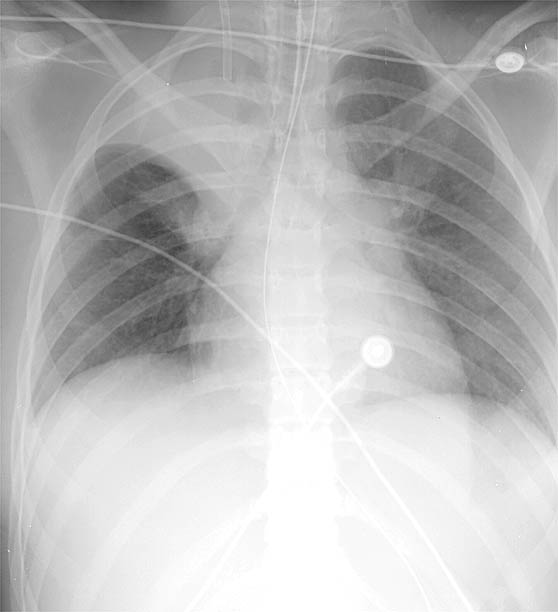

RUL Collapse Case 5 PA only